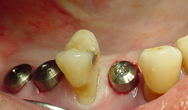

通常のインプラント手術では、メスを使った歯肉の切開や術後の縫合などが必要でした。フラップレス(無切開)手術とは、インプラント埋入部位の歯肉に小さい穴を開け、歯肉の切開剥離なしにインプラントを埋入する手術方法です。

これにより、外科手術に抵抗のある患者様の恐怖心を軽減することが可能となりました。 切開や縫合を行わないため、非常に短時間で手術を行なうことができ、切開や糸で縫うことからくる「腫れ」や「痛み」、「出血」が少ないのも特徴です。

ただし、フラップレス手術は、歯肉の上から骨を見ずに行なわれる手術であるため、他のインプラント手術以上に歯科医師の経験や高度な技術が求められ、CT撮影によるシミュレーションなど事前の念入りな診断が不可欠です。